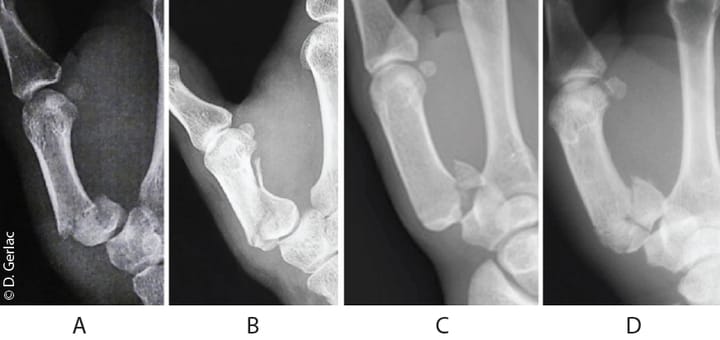

Rééducation Rééducation après fracture du premier métacarpien (Bennett, Rolando) : quel protocole aujourd'hui ?